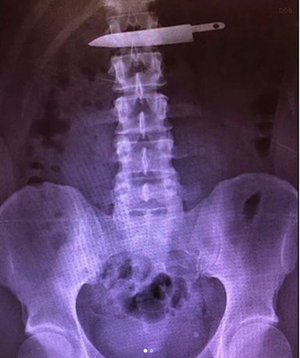

The back story behind this bizarre X-ray was the patient got into a fight with his significant other and attempted to swallow the blade off of his steak knife. It was eventually removed via endoscopy. Unfortunately he returned several weeks later after swallowing another larger blade (swipe right) and at that time had to have an emergency abdominal surgery to remove it.Photo credit @e_wigs